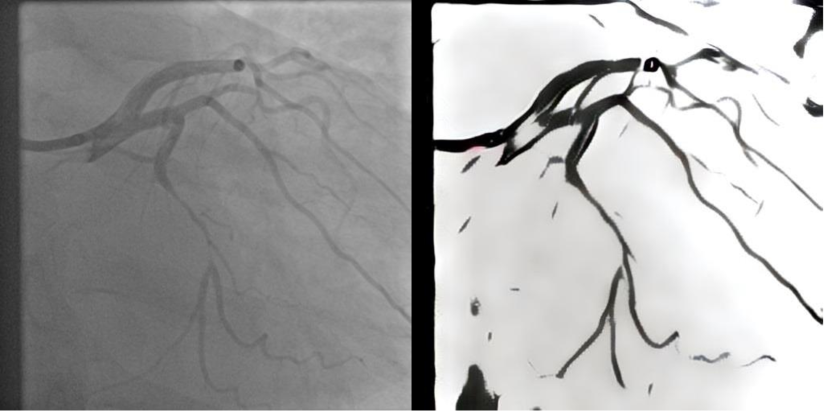

Another creative approach to image segmentation using GANs was proposed in [44]. The authors used a popular style transfer network with an Adaptive Instance Normalization layer [81] and added Convolution Block Attention Modules [82] and DexiNet [83] for improved style transfer performance. Uniqueness of this method lies in the extremely fast inference time and high accuracy of 0.96580.96580.9658, which was tested using both open datasets described earlier [42, 43]. This method does not require ground truth images, which were labelled by medical professionals for training purposes. Furthermore, it produces segmented images using style transfer from black and white drawings, which are taken from the BSDS500 dataset [84]. The result of style transfer using AdaIN network for XCA segmentation task can be observed on Fig. 3.

Refer to caption

Figure 3: Sample segmentation using style transfer from open source black and white drawing using baseline AdaIN network. Original image on the left; Inference result on the right.